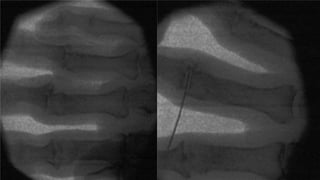

MCP JOINT

■ Under image intensifier

guidance, after ring block

anaesthesia, the finger trap is

applied distally. With an

assistant applying traction, a

25G injection needle is

inserted into the joint under

fluoroscopy and the steroid

injected A point just dorsal to

the midlateral position is safe

and easy to enter the joint.